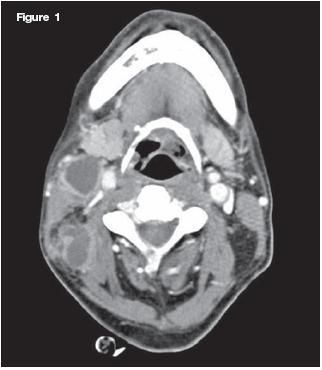

A 36-year-old woman with HIV infection had acute right-sided neck pain that progressed to swelling above the mandible. Ultrasound showed bilateral, anechoic, and primarily cystic lesions in the parotid glands. A CT scan detected a 3-cm, well-circumscribed, and homogeneously hypodense cystic lesion in the right parotid gland and a smaller, 1.2-cm multicystic lesion in the left (arrows). There were subcentimeter lymph nodes in the cervical and supraclavicular chains bilaterally. The condition can be a diagnostic indicator of underlying HIV infection.